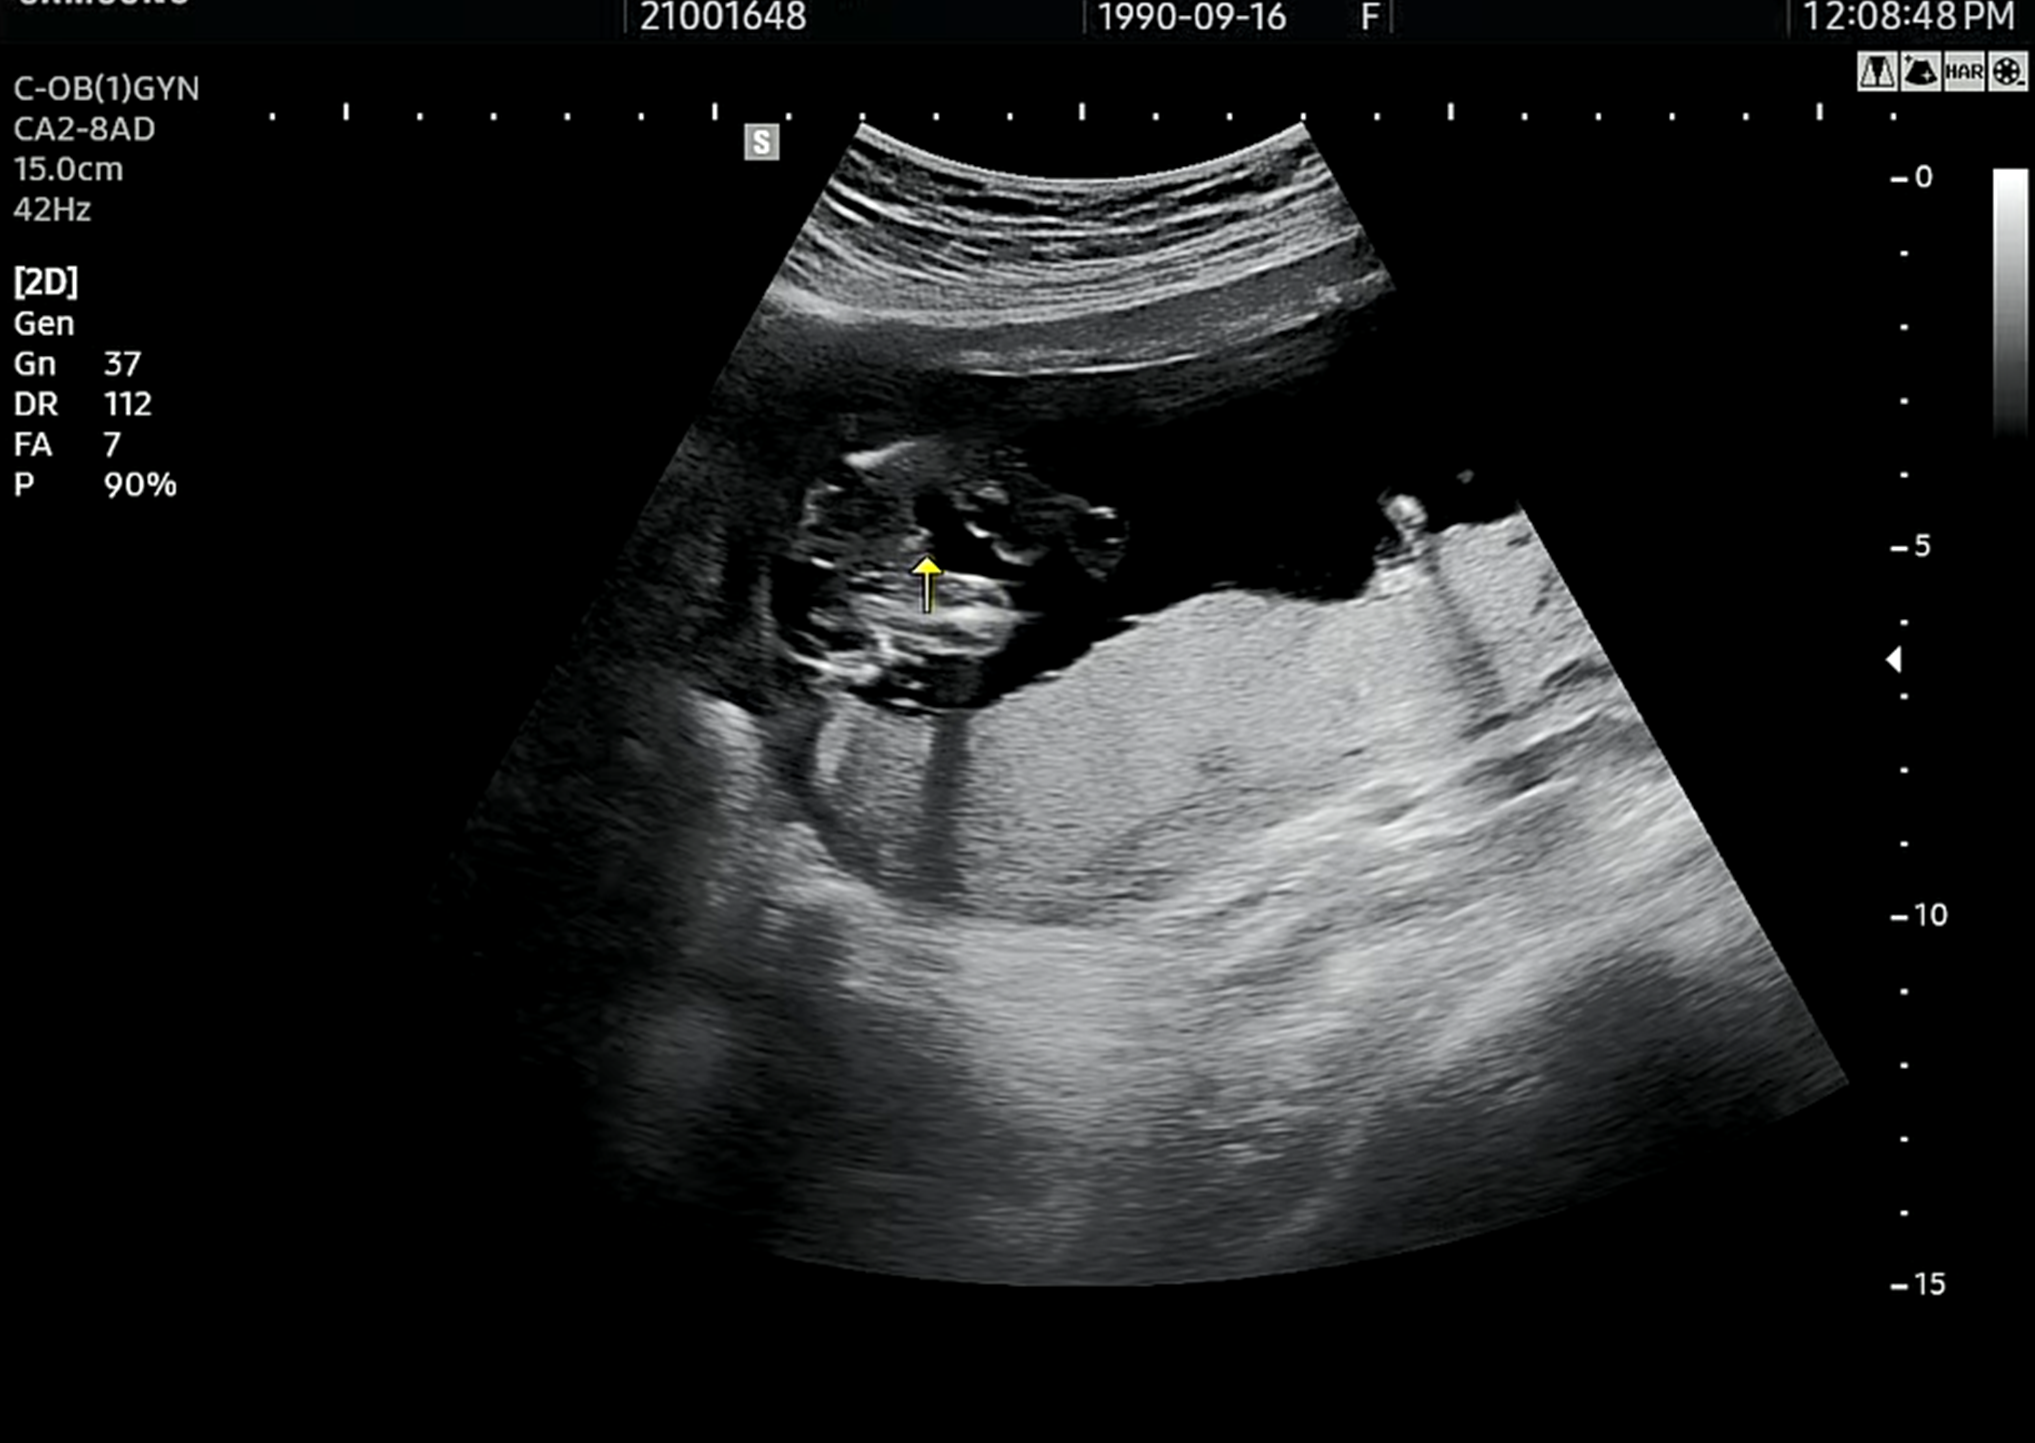

위의 초음파 사진을 보면 무언가 튀어나와있는 것을 볼 수 있다. 우리 호띵이는 아빠의 좋은 친구가 되어 운동이나 게임 및 다양한 일상생활을 같이 하라고 하늘에서 아들이 되게 해 주신 거 같다. 성별을 알게 되자마자 병원에서 나오는 길에 호띵이 할머니/할아버지와 통화를 하면서 성별을 알려드렸다. 남자아이라고 하니 가족들이 정말 축하해주고 좋아해 주셨다. 성별이 무엇이든 아직은 실감이 나지 않고 키워보면서 서로를 알아갈 것이기 때문에 아빠랑 처음 만나는 날까지 엄마 뱃속에서 건강하게 잘 자라기만을 바라고 있다.